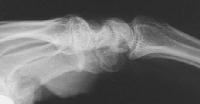

Plain films show dorsal impression of the capitate.